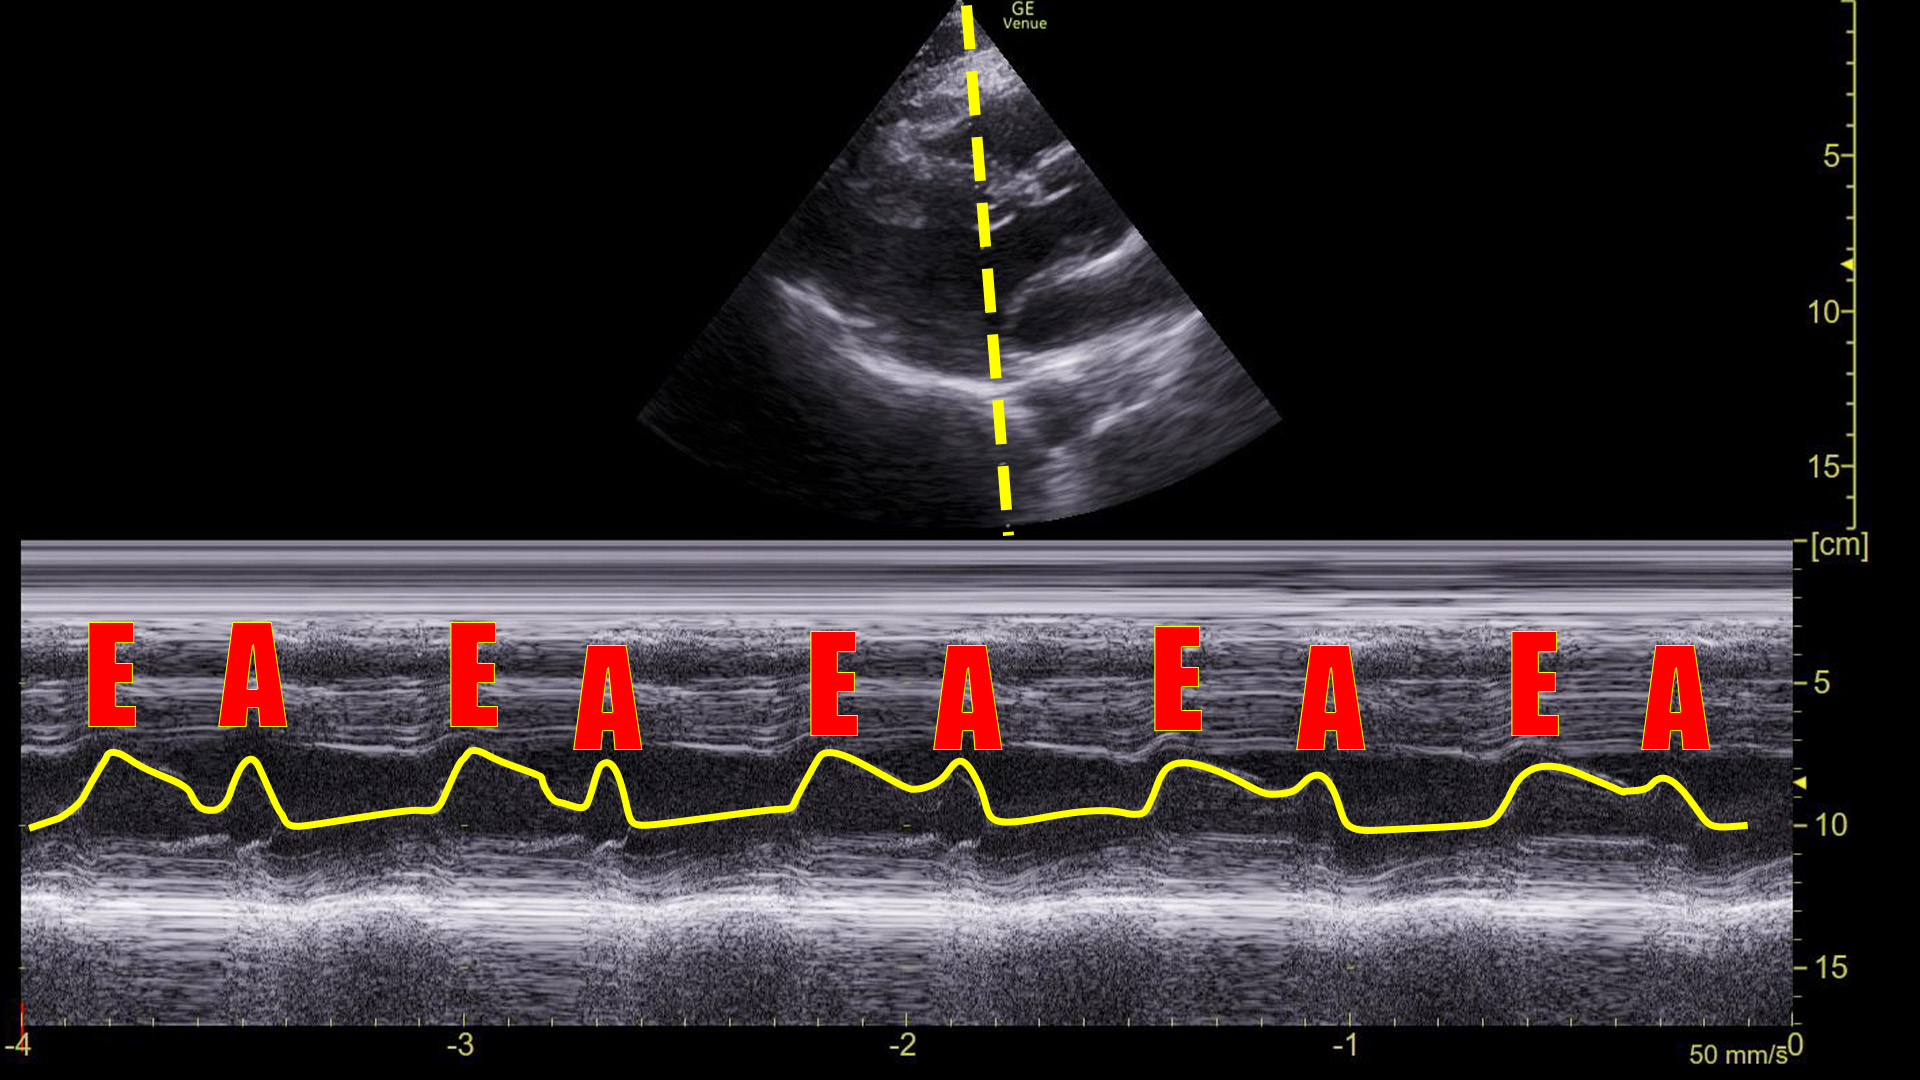

The machine read the ECG as sinus tachycardia, but I had my doubts. So, we obtained this M-mode tracing with the spike over the mitral valve in a parasternal long axis view.

This made it clear that he was in an arrhythmia. The rate was 153, so we assumed it is atrial flutter with 2:1 conduction, but just based on this image and the narrow QRS complex on the ECG, it could have been SVT or a strangely regular atrial fibrillation.

Here it is with the area of interest highlighted.

What we are looking at here is the movement of the mitral valve within the left ventricle – specifically what is highlighted in yellow is the movement of the anterior leaflet of the mitral valve. (Recall that it has two leaflets: anterior and posterior.)

You can see that the leaflet flaps once per cardiac contraction. That, however, is ABNORMAL!

We can see this on ultrasound as demonstrated above. Graphically on the screen, the first movement is called the E-wave, and the second is called the A-wave.

Compare that to the tracing before the cardioversion:

There are no A-waves.

This tells us that the atria are not contracting in an organized, functional way because the mitral valve is only flapping once during each heart beat.

In a sinus rhythm, we see E-waves and A-waves. This is a normal appearing tracing.

In a sinus rhythm, the mitral valve opens twice during ventricle filling: once during passive filling, then again during atrial contraction. We can see these two movements on an M-mode tracing with the spike placed through the anterior leaflet of the mitral valve on a parasternal long axis view of the heart. Graphically, the first movement produces a wave that is termed the E-wave; the second is the A-wave. Absence of the A-wave tells us that there is no atrial contraction, which would be seen in conditions like atrial fibrillation, SVT, atrial flutter, or ventricular rhythms.